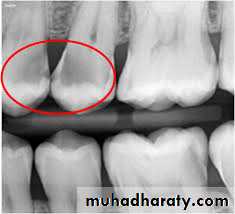

3. Radiography method

Types of X-ray radiograph images:• Periapical X-ray radiograph.

• Bitewing X-ray radiograph.

• Panoramic X-ray radiograph.